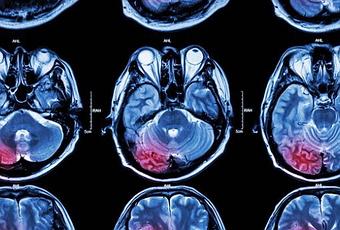

La resonancia magnética (RM).

Esta es probablemente la mejor herramienta de diagnóstico posible para la detección de aneurismas. Este tipo de imagen utiliza un campo magnético de ondas de radio para crear imágenes detalladas de cortes transversales del cerebro. Cuando esta prueba diagnóstica implica el uso de un contraste, se le conoce como la angiografía por resonancia magnética.